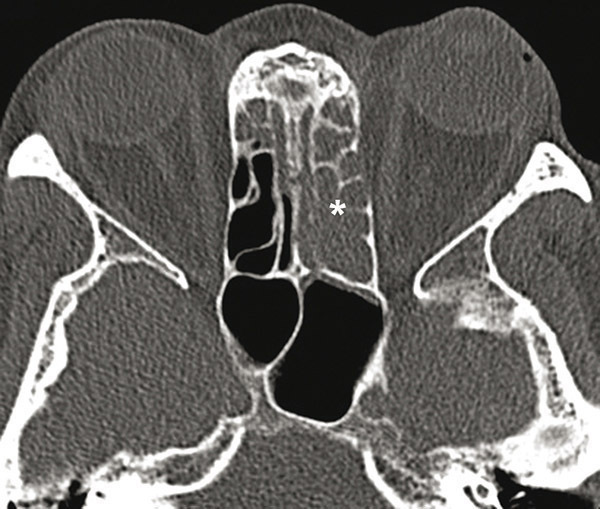

© Sylvain Poirée - La Revue du Praticien Tomodensitométrie des sinus de la face montrant un comblement du labyrinthe éthmoïdal à prédominance gauche (*).